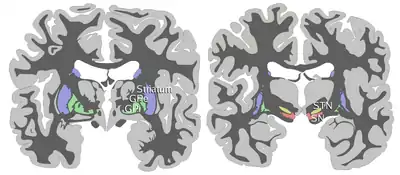

Coronal slices of human brain showing the basal ganglia (external globus pallidus (GPe) and internal globus pallidus (GPi)), subthalamic nucleus (STN) and substantia nigra (SN). | |